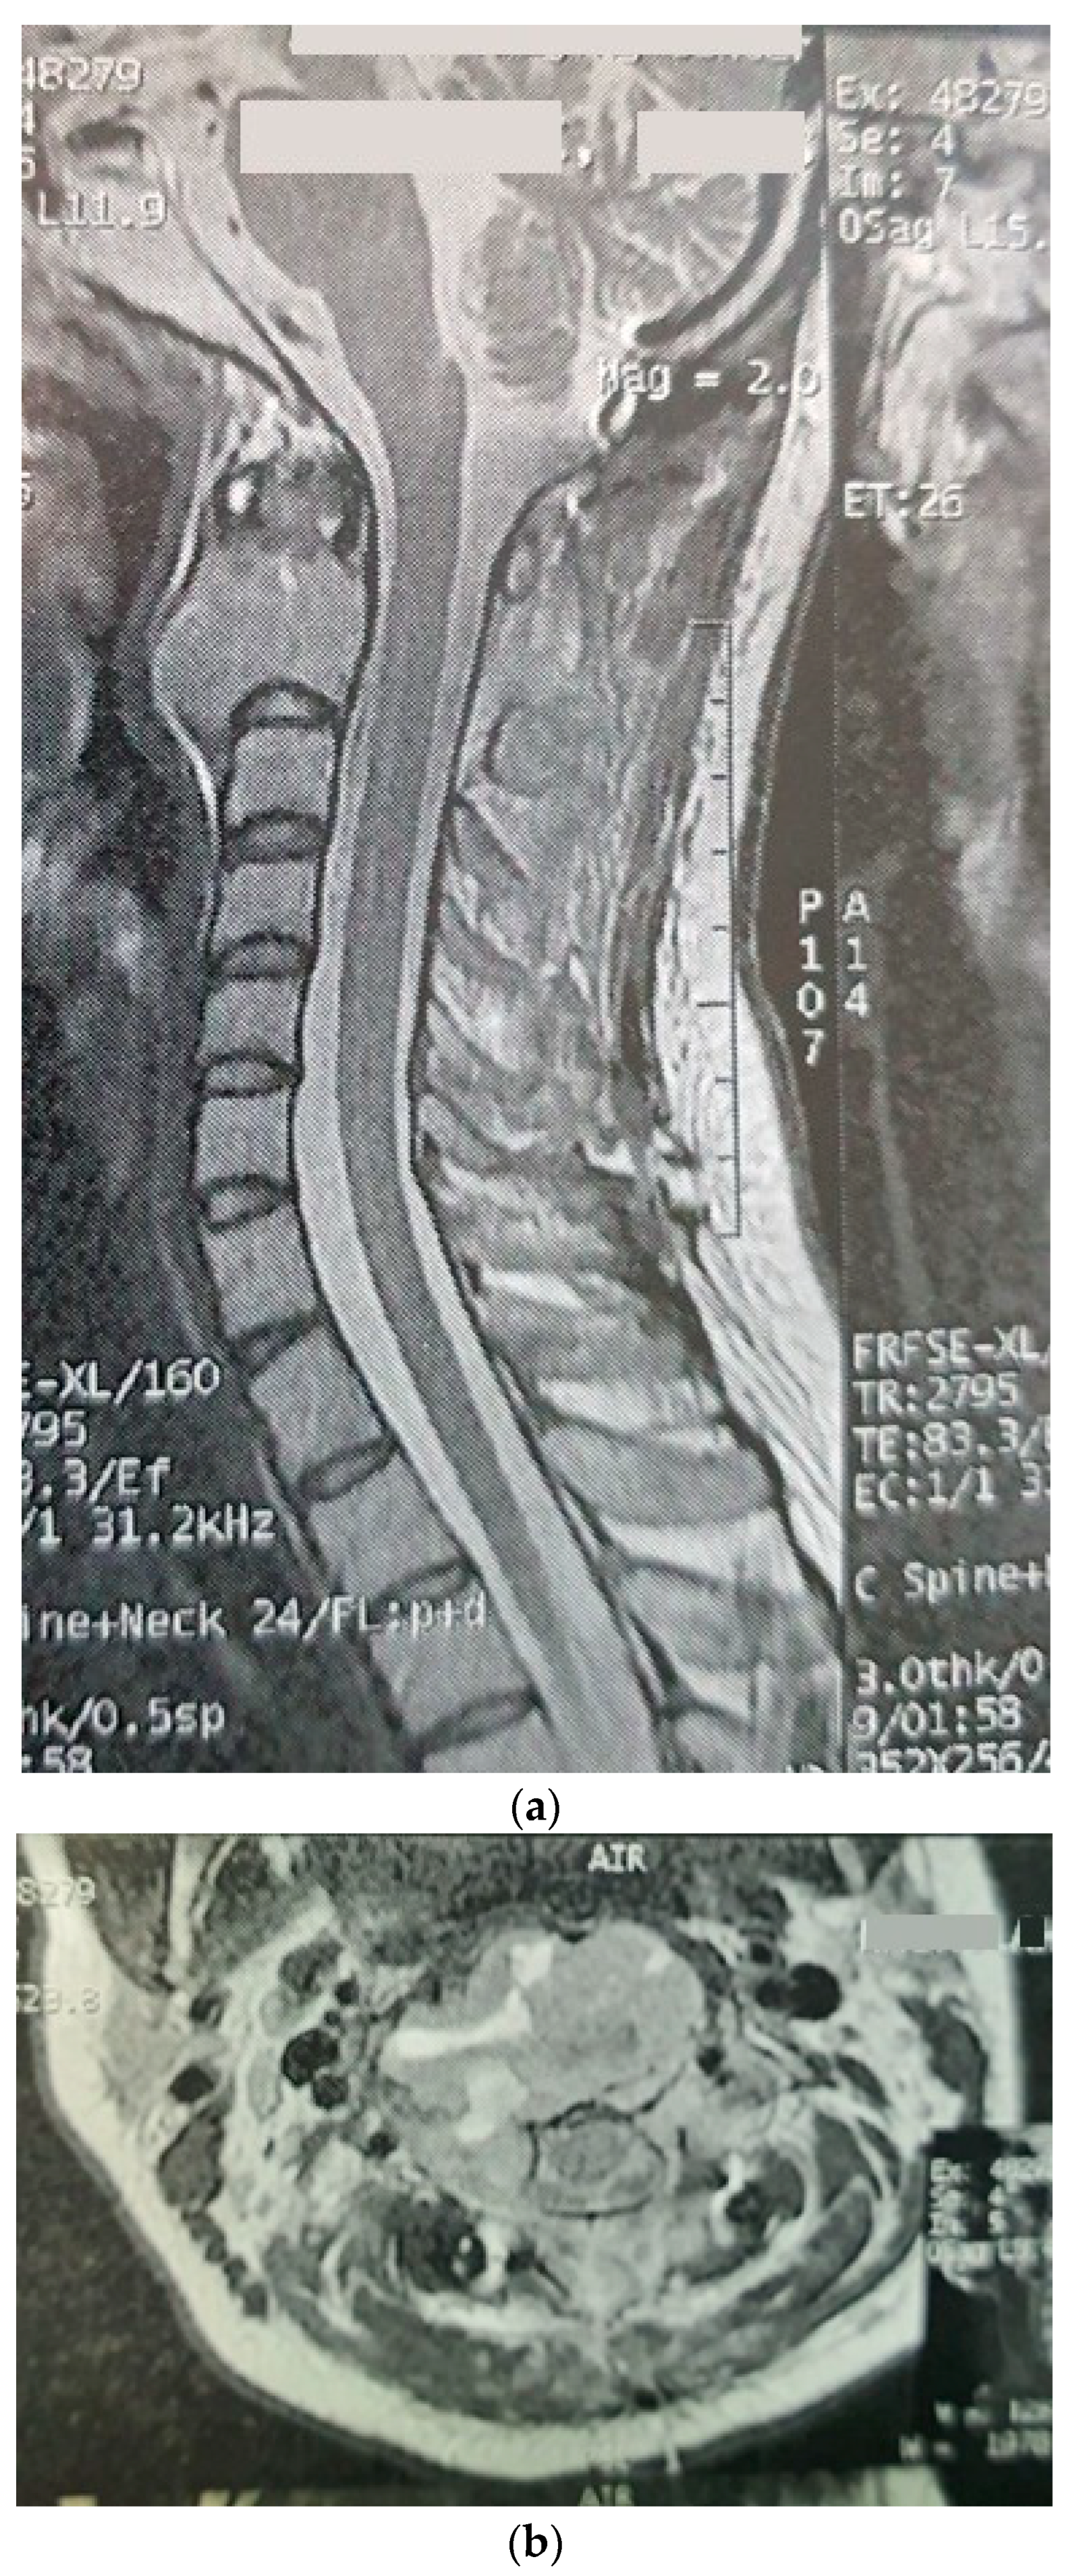

Three months later, the patient’s symptoms worsened, and she developed dysphagia. A repeat MRI showed a significant increase in the size of the tumor and a paravertebral extension (35 × 43 × 48 versus 52 × 42 × 60) (Figure 2). This time, an anterior approach was chosen for tumor decompression. There was cellular infiltration of the stroma characterized by sheets of large cells with abundant cytoplasm and rather distinct cell borders. Highly pleomorphic and sometimes hyperchromatic single nuclei were seen. Within the cytoplasm of most of the tumor cells, there were abundant partly degenerated RBCs. Scattered lymphoid cells were also present in the stroma. Some of the particles were bordered by tiny bony trabeculae. No necrosis was seen. Eight to ten mitoses per high power field with few atypical mitoses were detected, and the diagnosis of malignant HS was made. In the immunohistochemistry, cells were positive for CD45, CD43, CD68, and S100 (S100 negativity in the first operation may be due to the small size of the sample) and negative for CD3, CD20, and cytokeratin (Figure 3). The metastasis workups (thoracic and abdominopelvic CT scan) and bone marrow biopsy were normal. To deal with this new reported pathology, 25 sessions of radiotherapy (IMRT) in 5 weeks were considered for the patient to a total dose of 45Gy.

Figure 2.

Sagittal (a) and axial (b) gadolinium-enhanced MRI after the progression of the tumor that caused severe dysphagia.

Post-radiotherapy MRI, sagittal T2W (a), sagittal T1W (b) showing a very good response to treatment.